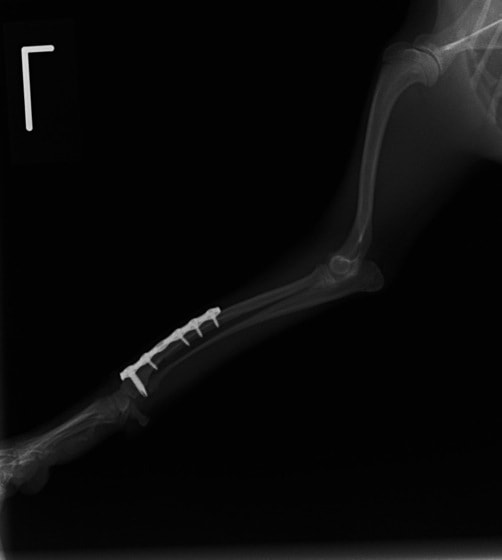

トイプードル 右遠位橈尺骨短斜骨折のALPSによる内固定

当院ではAdvanced Locking plate system(ALPS)と、Locking compression plate system(LCPS)という骨接合法で骨折症例の治療を行っています。

従来型のプレートのように広い面積で骨と接するプレートを用いて固定を行った場合、プレート下の骨はプレートとの接触面において血行が絶たれ壊死し、それがリモデリングされると骨密度が低下する。この骨密度の低下防ぐために、骨折部局所への血行を温存することの重要性が近年改めて認識されるようになってきている。Advaed Locking Plate System (ALPS)は従来型のプレートシステムの欠点を改良し、より使いやすく、より骨への血行を阻害しないようにというコンセプトで作られた。

- ロッキングスクリューと圧着型スクリュー(皮質骨スクリュー)の双方が使用できる